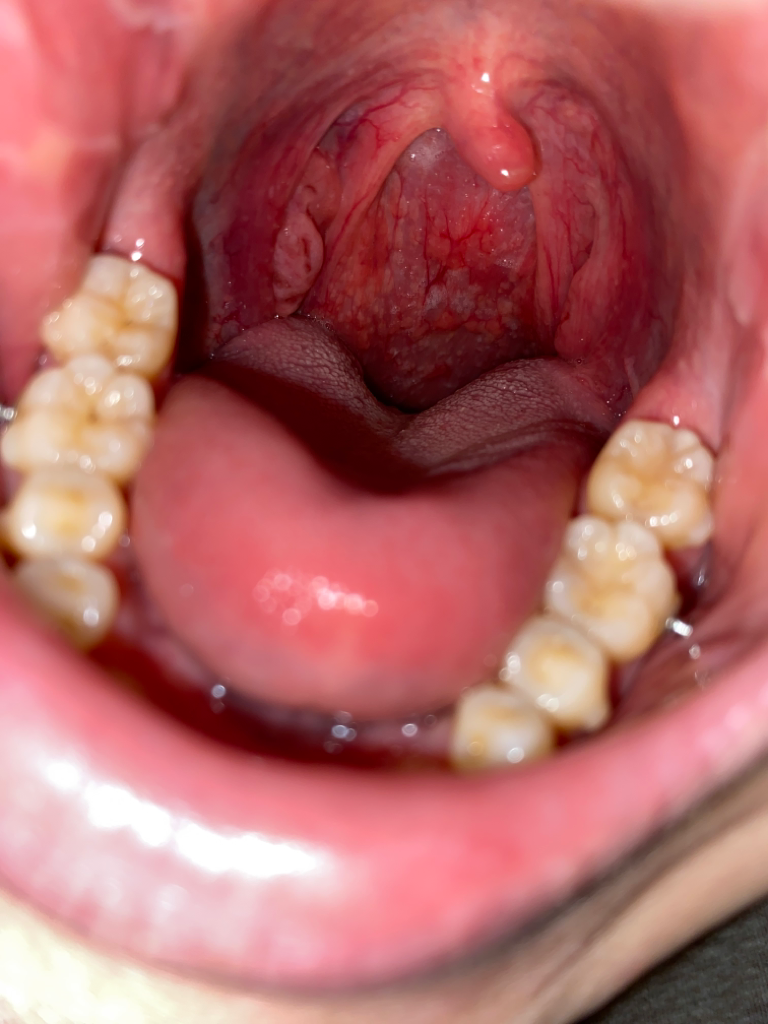

구인두 후벽에 난거 정상일까요?

편도선 옆에 보면 뭔가 하얗게 오돌토돌 올라온거같아 보입니다. 발견한건 2일 전이고, 목이 좀 칼칼한게 있지만, 딱히 별다른 통증은 없습니다.

병원에 가봐야 할까요 아니면 좀 더 지켜봐도 괜찮을까요?

정사적인 편도가 원래 저렇게 보입니다.

이상소견이 없으니 걱정 안하셔도 되겠습니다.

목이 건조한건 환절기 건조함때문일 수 있으니 따뜻한 물을 많이 먹어서 습도를 올려주시는게 도움이 되겠습니다.